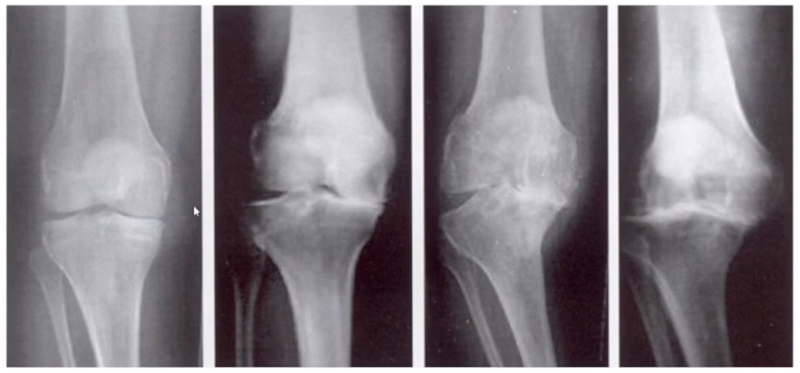

牛津单髁影像学判断的标准为通过负重正位片来判断内侧间室关节软骨的磨损程度。内侧间室关节间隙变窄,股骨内侧髁与内侧胫骨平台成“骨磨骨”状态,说明内侧间室软骨磨损丢失。如果没有在正位片观察到“骨磨骨”,则需要通过内翻应力位片或rosenberg位检查,找到骨磨骨的证据。如果以上均没有显示骨磨骨,需考虑关节镜检查,只有在达到“骨磨骨”的情况下才考虑行UKA。

AMOA查体与X线特点,站立位屈曲内翻

AMOA的X线正位的表现